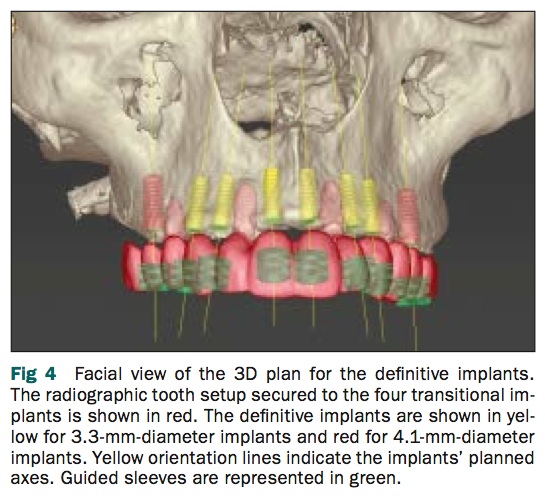

關於這篇文章提到的方式, 在我剛畢業的時候我就有看過了, 但在paper上比較少看到有系統地去設計使用這樣的方式做單顎或是全口的植牙重建治療. 因為重點都在圖表所以也是請看圖說故事, 其重點就是若有transitional implant (犧牲打的implant), 不但可以讓患者在植牙的時候手術模板夠穩定, 還可以讓臨時假牙穩定有作用.